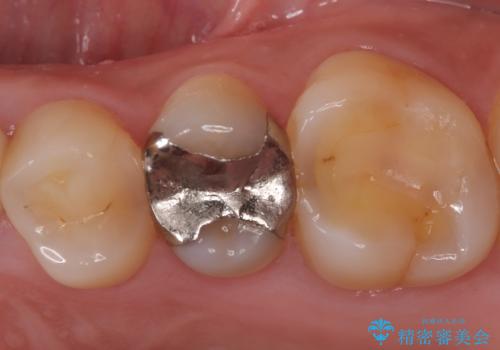

銀歯の下に虫歯 〈オールセラミッククラウン〉

- 初診時に金属の下に虫歯があることを指摘しました。もともとの詰め物の形と虫歯の大きさから被せものでの治療となりました。見た目、材質の説明をし、セラミッククラウンでの修復となりました。

メタルインレーが入っていたこと、う蝕が大きかったこと、頬側にHysに対してのCRがあったことを踏まえてクラウンでの修復を選択しました。